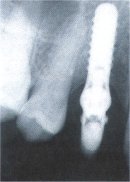

Fall Nr. 2 Nur auf dem Röntgenbild ist etwas zu erkennen, was sich unter diesem Zahn verbirgt: Ein Implantat. Fall Nr. 2

Die einzementierte Krone fügt sich in Farbe und Form harmonisch in die bestehende Zahnreihe ein.